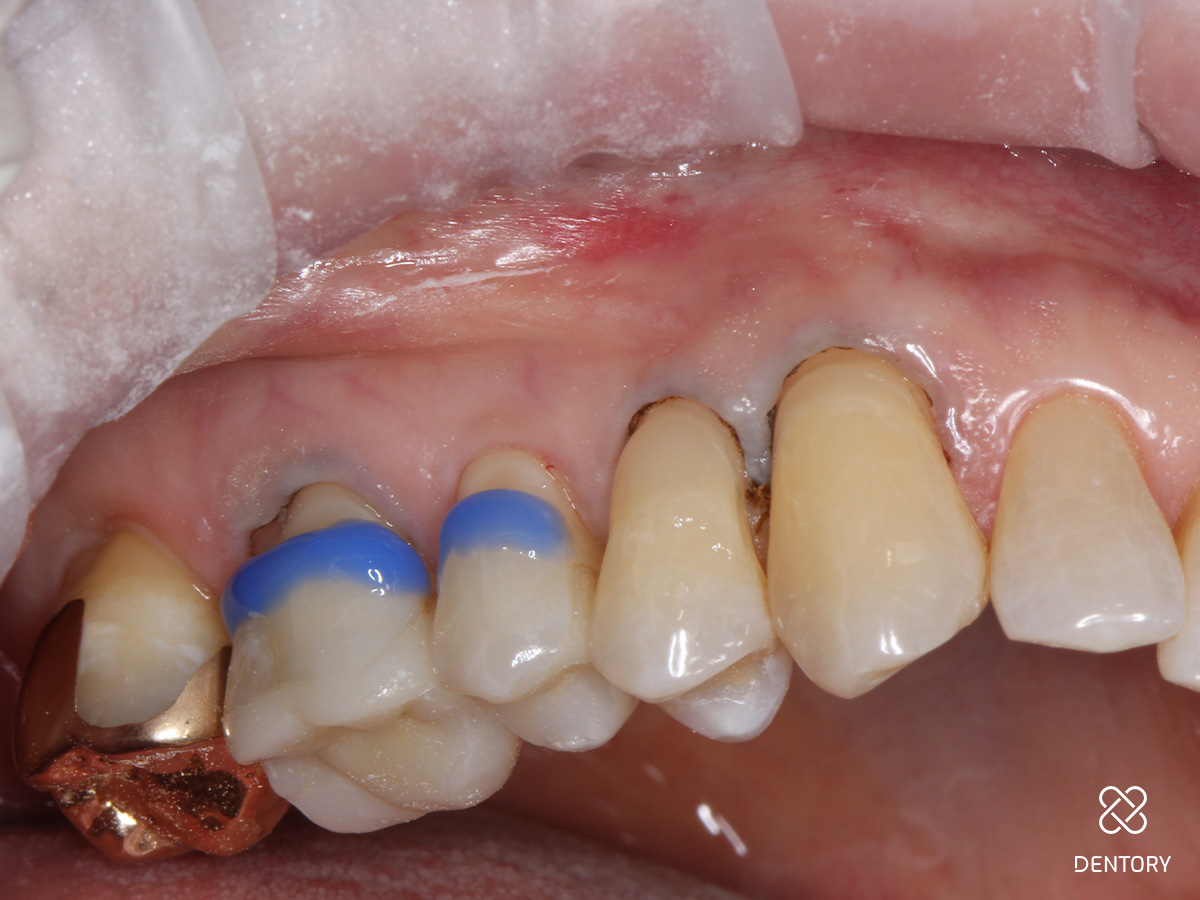

Abbildung 4

Es erfolgt die Schmelzätzung - nach ca. 10 Sekunden dann die Dentinätzung - nach 30 Sekunden die saubere Entfernung des Ätzgels. Überreste werden nach zervikal abgesaugt, danach erfolgt die Lichthärtung für 20 Sekunden.